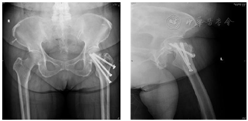

3.2016年3月 患者取出一枚空心钉后,再次跌倒,发生左侧股骨粗隆下骨折。在骨折远端边缘有鸟嘴样皮质增厚改变,此为股骨不典型骨折的特征表现(图3)。

4.2016年3月双髋关节正侧位X线片 行左侧股骨粗隆下骨折闭合复位髓内针内固定术,骨折断端复位欠佳,骨折断端仍有间隙(图4)